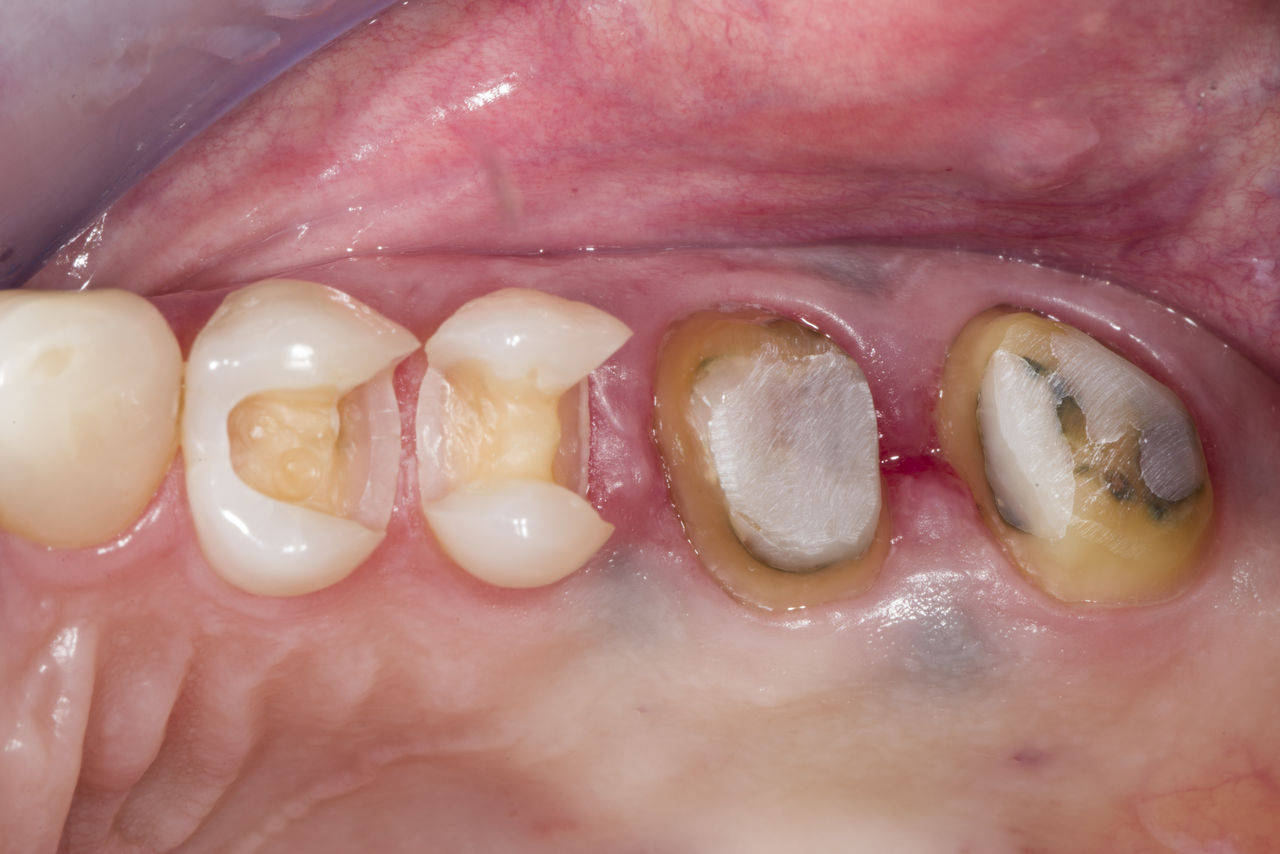

Before: Failed amalgam restoration needing replacement. Patient complaining of sensitivity and tooth presenting multiple cracks.

After: Chairside CAD/CAM partial crown restoration fabricated with CEREC Tessera Advanced Lithium-Disilicate glass ceramic.